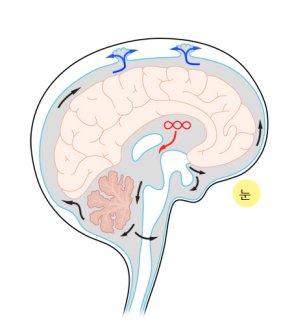

뇌에는 뇌척수액(cerebrospinal fluid, CSF)이라는 맑은 체액이 뇌의 안과 밖을 채운 채 순환하고 있다. 뇌의 안쪽에는 뇌실(ventricles)이라는 작은 빈 공간들이 있으며 이 곳에 있는 맥락총 혈관(choroids plexus vessels)에서 뇌척수액이 만들어진다. 뇌척수액은 혈액에서 적혈구나 백혈구 세포들이 제거된 혈장과 비슷한 액체이며, 생성된 뇌척수액은 뇌실의 구역을 따라 흘러서 소뇌 주변의 제4뇌실의 출구(basal foramina: foramina of Luschka and Magendie)를 통하여 뇌의 바깥쪽으로 나오게 된다. 뇌척수액은 척수 주변의 지주막하 공간(subarachnoid space)을 순환하고 뇌의 아래쪽 지주막하 공간(basal cisterns)을 지나 대뇌 표면의 지주막하 공간으로 모여 양 대뇌 반구 사이 천정을 지나는 상시상 정맥동(superior sagittal sinus) 안으로 흡수되어 혈액으로 되돌아간다. 뇌척수액은 뇌를 충격으로부터 완충하는 쿠션의 역할을 하고, 두개강 내의 압력을 골고루 분산하는 역할도 하며, 영양분이나 노폐물을 운반하는 역할도 하는 것으로 알려져 있다. 정상적으로 하루에 약 500ml의 뇌척수액이 만들어져 순환하고 있으며, 뇌와 척수 주변에 존재하는 뇌척수액의 총량은 신생아는 약 50ml, 소아는 약 100ml, 성인은 약 150ml 정도이다. 어떤 원인에 의하여 뇌실 내 맥락총 혈관에서 마지막 상시상 정맥동에 이르는 뇌척수액의 순환로가 일부 막히게 되면 뇌척수액이 두개강이나 척추강에 비정상적으로 축적되게 된다. 뇌척수액의 축적은 대부분의 경우 뇌압의 상승으로 이어지며 이로 인한 증상과 뇌 발달의 장애를 일으킨다. 급격한 뇌압 상승은 생명을 위협할 수도 있다. 선천적인 뇌와 척수의 구조 이상과 연관되어 나타나는 경우가 많아서 소아에게 많이 발생한다. 그러나 뇌출혈, 뇌종양, 중추신경계 감염과 같은 후천적인 질병과 연관된 경우는 소아뿐 아니라 성인에서도 나타나며 노인에서는 미세한 뇌척수액 순환장애로 인하여 뇌압이 높아지지 않는 가운데 뇌척수액이 축적되는 독특한 형태의 수두증이 나타난다. 뇌실에서 지주막하 공간에 이르는 길이 막혀있는 경우 뇌실만 확장되는 비교통성(non-communicating) 수두증이 발생하고, 제4뇌실의 출구 이후에 지주막하 공간에서 폐색이 있는 경우 뇌실과 지주막하 공간이 모두 확장되는 교통성(communicating) 수두증이 발생한다. 이 분류는 치료 방법을 결정하는 데 중요한 기준이 되기도 한다.

뇌척수액의 흐름